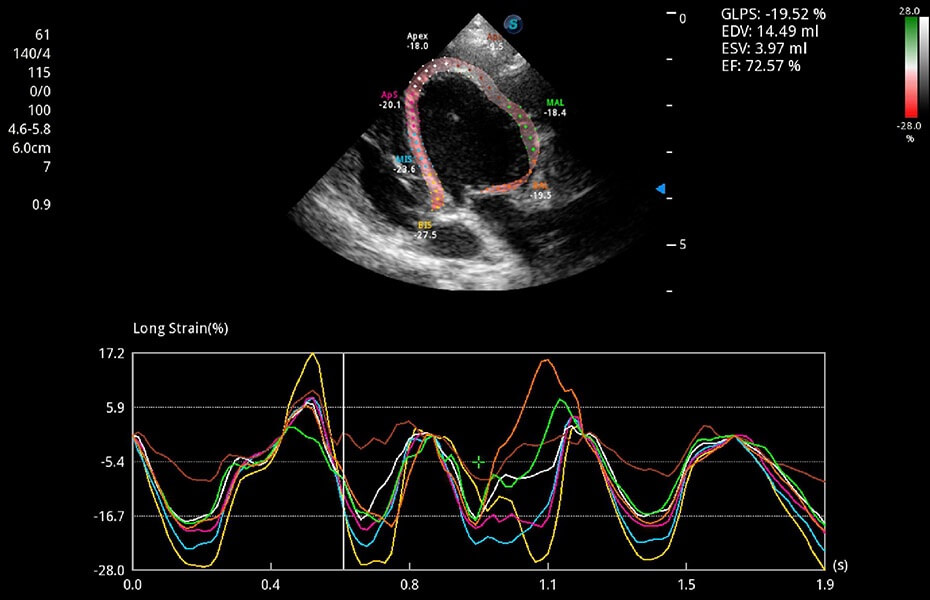

ProPet 60 作為一款高端臺(tái)式動(dòng)物超聲設(shè)備,為動(dòng)物醫(yī)生的日常診斷提供了一系列貼合動(dòng)物臨床需求、解決臨床實(shí)際問題的高級成像功能。憑借全系列高清探頭,滿足醫(yī)生對腹部、心臟、生殖、淺表、肌骨等成像的所有需求,切實(shí)幫助您提升檢查效率,提高診斷信心。